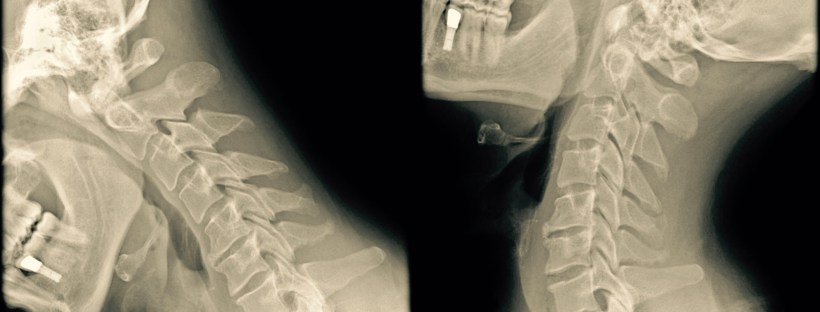

radiographie cervicale avec mouvement

Votre colonne vertébrale a trois grands rôles : bouger, stabiliser votre corps et surtout protéger votre système nerveux. Il faut un traumatisme très important pour briser ou déplacer une vertèbre et quand cela arrive, c’est une vraie catastrophe. On parle alors de paralysie de certains membres.